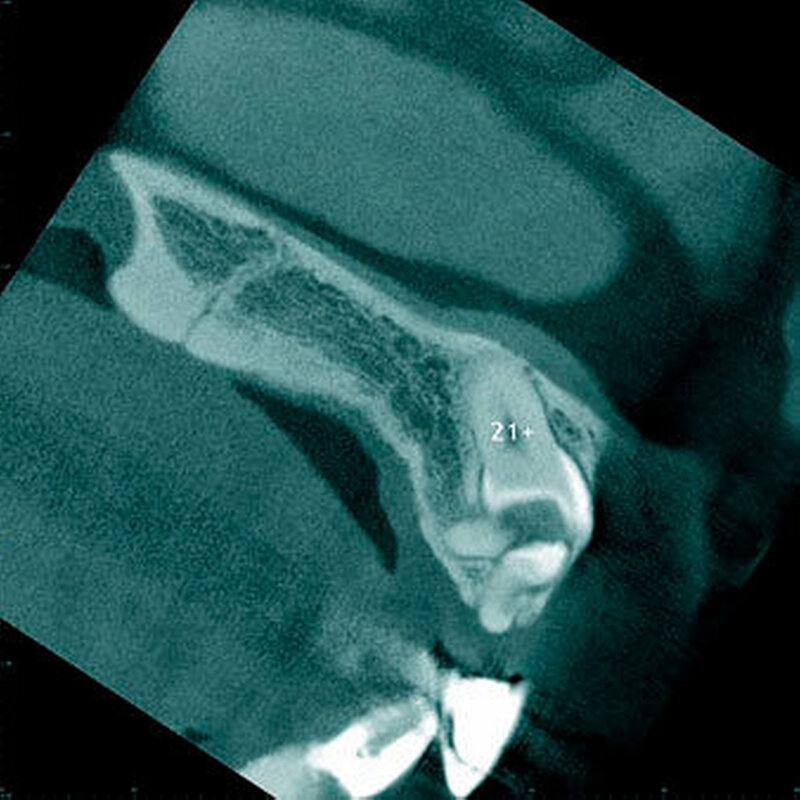

Radiologisch erscheint der Zahnfollikel um retinierte überzählige Zähne als eine dünne perikoronale Radio-luzenz, welche in der Regel nicht breiter als 3 mm ist [Mossaz et al., 2014] (Abbildung 19). Andere Autoren betrachten eine Breite von 2 mm als physiologisch [Tyrilogou et al., 2005]. Bis heute fehlen aber klare Angaben zu den normalen Dimensionen des Zahnfollikels, das heißt, es ist radiologisch nicht eindeutig zu erkennen, wann ein zystischer Prozess vorliegt [Villalba et al., 2012]. Studien berichteten über eine (pathologische) Erweiterung des Follikularraums in 1,4 Prozent bis 5,3 Prozent der überzähligen Zähne [von Arx 1990; Tyrologou et al., 2005; Liu et al., 2007; Hyun et al., 2009; Mossaz et al., 2014]. Dagegen sahen Koch und Mitarbeiter (1986) bei 54 überzähligen Zähnen keine Erweiterung des perikoronaren Raumes während des Beobachtungsintervalls (Mittelwert: 7,3 Jahre).